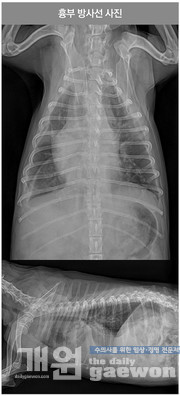

흉부 방사선 촬영상 흉수와 심비대증이 확인 되었으며, 복부 방사선 촬영상 뚜렷한 간비대증 및 복수 소견이 보였다.